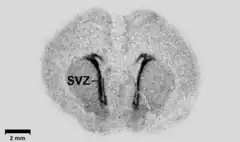

- ↑ Haydar TF, Wang F, Schwartz ML, Rakic P (August 2000). "Differential modulation of proliferation in the neocortical ventricular and subventricular zones". J. Neurosci. 20 (15): 5764–74. doi:10.1523/JNEUROSCI.20-15-05764.2000. PMC 3823557. PMID 10908617.